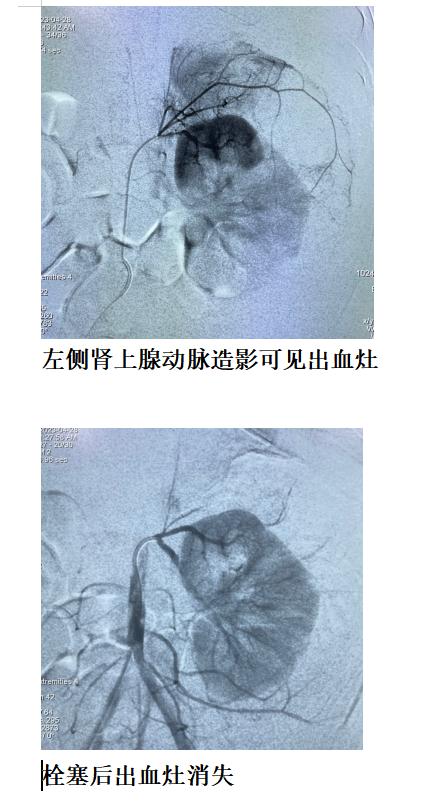

急诊在导管手术室,我们团队经皮穿刺股动脉,成功后置入穿刺鞘,选择肝动脉造影,确定无肝脏病灶出血;继而超选择左侧肾动脉造影,确定左侧肾上腺出血,微导管超选择肾上腺血管灌注栓塞剂后,造影示出血灶消失。手术顺利结束。